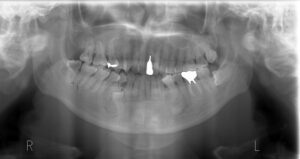

主訴 歯並びを治したい 治療方法 全顎的矯正治療 年代 40代 性別 女性 費用 矯正治療費 ¥990.000

ジルコニア冠 ¥165.000治療期間 32ヶ月 来院回数 1回/月 メリット 奥歯だけで噛んでいたため負担が強く、奥歯の治療を繰り返している。矯正治療により全体で咬合を負担できる。 リスク すでに神経のない歯もあり、夜間のナイトガードは必須。埋伏している右下の過剰歯を利用するため矯正期間は長期となる。 -

右下4番の根尖に過剰歯を認め、矯正治療による歯の動きを邪魔してしまっているとともに4番の根尖を吸収しているように思われたため、抜歯をして過剰歯を利用。

マイクロスコープの拡大明視野下で矯正用のボタンをセットする。 歯冠の形が歪で周囲の歯槽骨に引っかかってなかなか萌出してこなかったため、少しだけ亜脱臼させたあと矯正力をかける。

根管処置後、歯槽骨の回復を待つ。この時点では歯の動揺はかなりあり、抜けてしまうんではないかと思うぐらい。

感染が取れ、過度な咬合力がかからなければ歯槽骨も回復してくる。動揺もなくなる。

右下の親知らずを抜歯して、そのスペースに前方に倒れた大臼歯と小臼歯を起こし、できたスペースに犬歯を動かしたいのだが、埋伏している過剰歯が邪魔して犬歯を含め前歯を動かすことができない。埋伏している過剰歯を抜歯することができればもっと早く歯並びを変えることができたが、第1小臼歯を抜歯して、埋伏している過剰歯を利用しなければ矯正治療を行ってもうまく噛むことができない。時間がかかってしまい患者さんも本当に大変だったと思います。ご苦労様でした。矯正治療に関するページはこちら